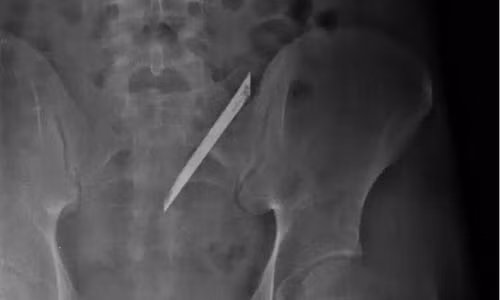

Ê-kíp bác sĩ khoa Ngoại tổng quát bệnh viện Nhân Dân 115 (TP.HCM) vừa phẫu thuật lấy lưỡi dao Thái Lan dài 12 cm nằm trong lưng 4 năm của anh Quang (tên bệnh nhân được thay đổi, 24 tuổi, ngụ quận 6).

Trước đó, anh Quang thấy đau lưng kéo dài nên tới cơ sở y tế chụp CT scan thì phát hiện có dị vật bên trong.

| Lưỡi dao dài 12 cm qua hình chụp CT scan. |

Nam thanh niên sau đó tới bệnh viện 115 phẫu thuật lấy dị vật là lưỡi dao nhọn ra ngoài.

Anh Quang kể, 4 năm trước anh có xảy ra xô xát với một nhóm thanh niên rồi bị đâm trúng. Ở bệnh viện địa phương, anh được bác sĩ khâu vết thương rồi cho về vì thấy vết thương không nghiêm trọng, cũng không chụp phim X-quang.

Từ đó đến nay, anh thấy hơi đau vùng lưng nghi do thời tiết thay đổi, có khi không thấy đau gì cả. Gần đây khi tình trạng đau nhiều hơn, anh mới đi bệnh viện kiểm tra.

Theo bác sĩ khoa ngoại tổng quát, đây là trường hợp hi hữu. Lưỡi dao dù đã nằm lâu năm trong cơ thể người bệnh nhưng không đâm vào cột sống, nên không ảnh hưởng đến thần kinh.